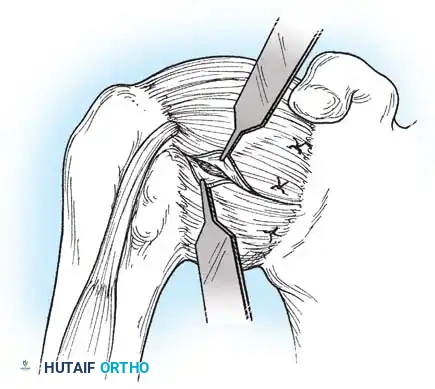

Subscapularis Management

Exposure of the anterior capsule requires navigating the subscapularis muscle. Historically, a vertical tenotomy was performed; however, modern techniques favor a subscapularis split or a peel to preserve the integrity of the muscle belly and its tendinous insertion.

- The Split: A horizontal split is made in the subscapularis at the junction of its middle and inferior thirds, extending from the lesser tuberosity medially.

- Separation: The subscapularis is carefully elevated off the underlying anterior joint capsule. This plane can be scarred in revision cases, requiring meticulous sharp dissection to avoid inadvertent capsulotomy.